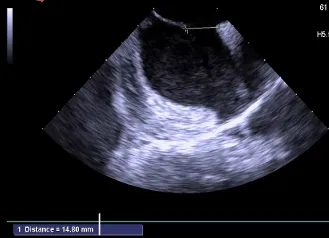

房间隔总长44.22mm,缺损大小14.80mm

超声可见房间隔连续中断,彩色多普勒可见过隔血流